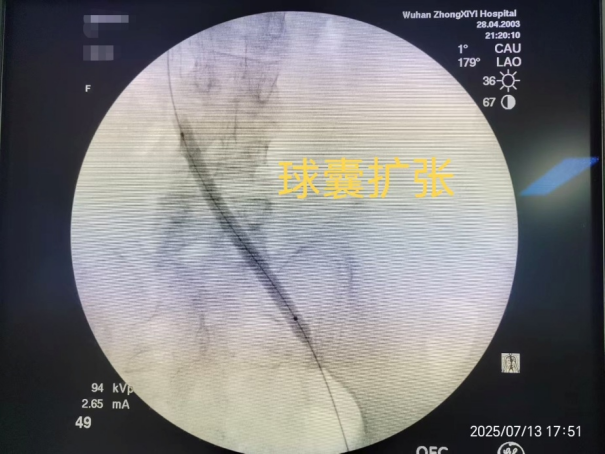

第二步:等到患者可安全抗凝后,再使用球囊扩张狭窄的髂静脉并植入支架,从根本上解决“血管狭窄”的问题。